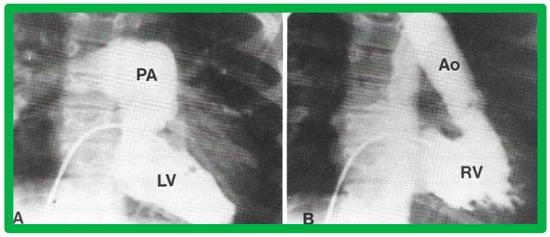

In theory, patients with cardiac malposition may have one (single) or two ventricles. The distinction between one and two ventricles is feasible by echocardiography (Figure 30) and angiography (Figure 31 and Figure 32).

Figure 31. Selected angiographic images demonstrating characteristic features of the right (A) and left (B) ventricles. The right ventricle (RV) exhibits coarse trabeculations (A), while the left ventricle (LV) shows smooth or fine trabeculations (B). In addition, the RV exhibits a triangular shape, whereas the LV is a foot-shaped structure. The tricuspid (TV) and pulmonary (PV) valves (arrows in (A)) are separated by a muscular structure, crista supraventricularis. Aorta (Ao) and pulmonary artery (PA) are labeled. Modified from reference [3].

Ventricular Trabeculations and Shape

The morphologic LV is a smooth-walled structure with fine trabeculations and a foot-shaped appearance, whereas the morphologic RV has coarse trabeculations and a triangular shape. These features are demonstrated by echocardiographic (Figure 34) and angiographic (Figure 31, Figure 35 and Figure 36) studies. It should be noted that the characteristic trabecular pattern of the ventricles is seen irrespective of great vessel relationship: normally related great vessels (Figure 31 and Figure 34), transposed great arteries in levocardia (Figure 35) or transposed great arteries in dextrocardia (Figure 36).

Figure 35. (A,B). Selected cine frames of the Left ventricle (LV) in posteroanterior (A) and lateral (B) projections of a child with d-transposition of the great arteries illustrating morphologic LV with fine trabeculations. The pulmonary artery (PA) originates from the LV. The pulmonary valve is positioned inferior and posterior to its normal position. (C,D). Selected cine frames of the right ventricle (RV) in posteroanterior (C) and lateral (D) projections of the same child shown in (A,B) illustrating morphologic RV with coarse trabeculations. The aorta (Ao) originates from the RV. The aortic valve is positioned superior and anterior (C,D) to its normal position. The closeness of the mitral with the pulmonary valve in a morphologic LV (A,B) and the separation of tricuspid and aortic valves in a morphologic RV (particularly in D) is clearly seen. Replicated from reference [35].